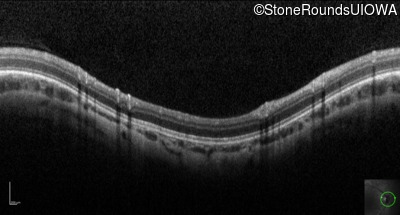

Optical Coherence Tomography - Right - 10/160 sc

Exemplar

Optical Coherence Tomography - Left - 10/200 sc

Exemplar / OCT Stack